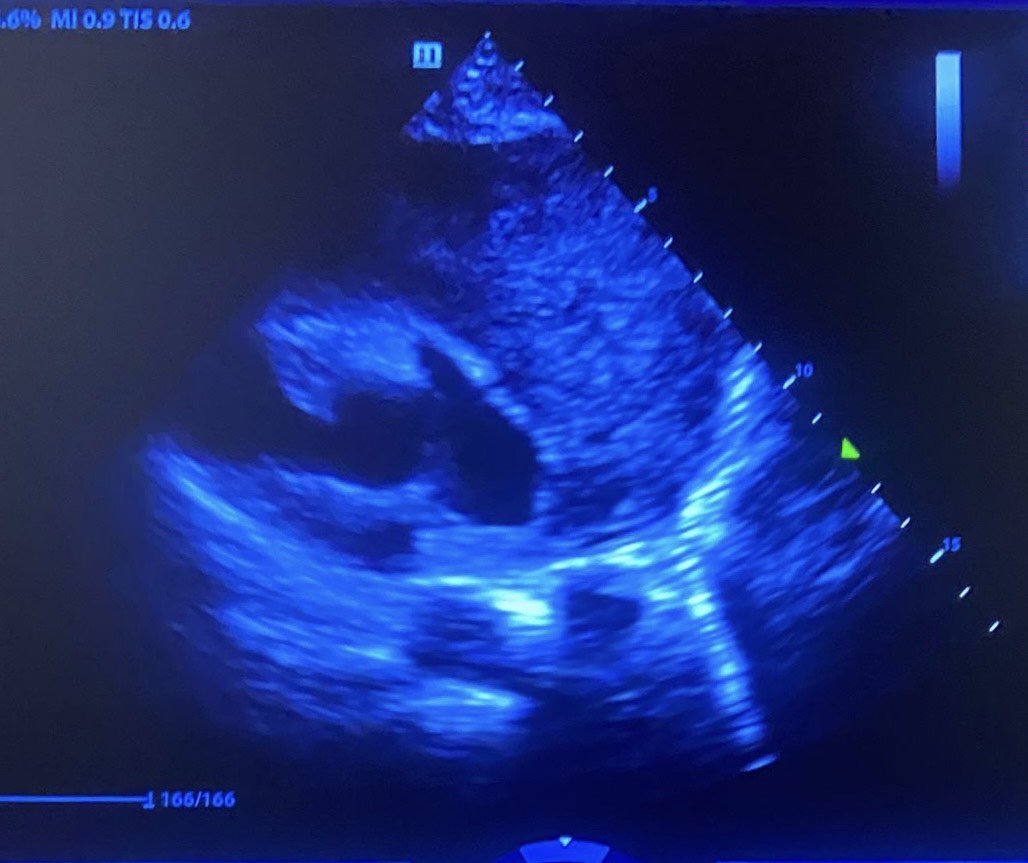

Ecocardiosopia: FEVI normal, ausencia de dilatación de cavidades derechas, sin datos de valvuloptía. Sin derrame pericárdico. En plano paraesternal eje corto masa homogénea e isoecogénica que rodea pericardio, con Doppler positivo.